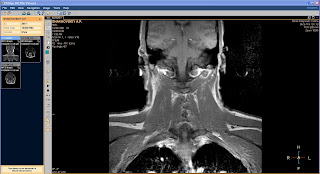

После загрузки наборов данных вы увидите в окне слева значки наборов данных, а справа в главном окне одно увеличенное изображение. Изначально будет выделен первый сверху значок. Выберите нужные вам данные для исследования и щелкните по соответствующему значку. В главном окне отобразится первое изображение выбранных данных, и вы можете приступать к исследованиям.

Вращайте колесо мыши и последовательно просматривайте изображения.

Функция интерактивного кино позволяет производить вручную прокрутку изображений перемещая мышь. Для начала работы в режиме интерактивного кино в панели инструментов щелкните по соответствующему значку.